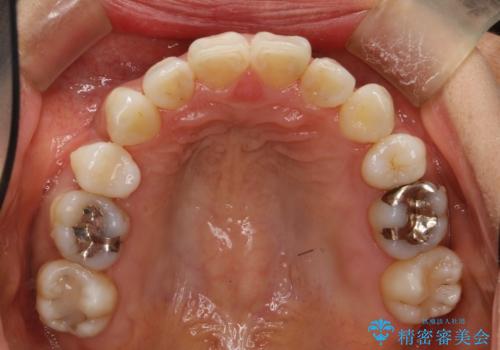

ハーフリンガル抜歯矯正 八重歯を改善する

シビアな八重歯がきれいに歯列にはいることにより、笑った時の印象などもかなり大きく変わります。